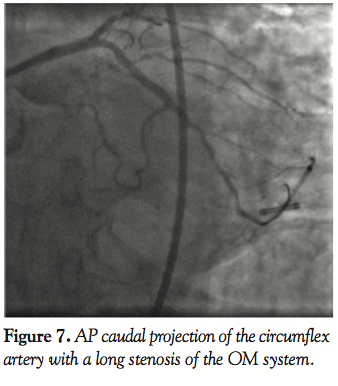

Case 3. A 65-year-old male presented with unstable angina. Diagnostic angiography demonstrated triple vessel coronary disease and normal ventricular function (Figure 7). After intervention on the RCA was performed, attention was turned to the circumflex artery (Figure 8). A 7 Fr EBU (Medtronic Vascular) guiding catheter was used for the intervention on the circumflex artery. A BMW (Abbott Vascular) guidewire was used to cross the lesion in the circumflex artery and angioplasty performed with a 3mm Voyager (Abbott Vascular) balloon. After

predilatation, there was difficulty advancing the stents through the calcified proximal vessel (Figure 8). A GuideLiner catheter was then advanced into the circumflex artery and this facilitated delivery of long drug-eluting stents to treat the stenosis successfully without need for a different wire or a different guiding catheter (Figure 9).

The GuideLiner catheter allowed a second vessel (circumflex) to be treated ad hoc by greatly simplifying a complex procedure and minimizing contrast load and radiation exposure to the patient. The patient was then brought back for treatment of the LAD chronic total occlusion. This enabled complete revascularization for this patient.

In the third, fourth, and fifth cases, the reason for the development of this device, facilitating distal stent delivery, is demonstrated. Commonly used methods to overcome difficulty with stent delivery include straightening of the vessel with a buddy wire, use of an anchor balloon, and using large diameter guiding catheters with more supportive curves. The GuideLiner facilitates delivery of stents to distal segments of the coronary vessel (Figures 4 and 5) by allowing safe deep vessel intubation. This provides the necessary extra back-up support needed for stent delivery. In an era when radial artery intervention is making a comeback into the mainstream, this may have added significance because the vast majority of cases via the radial artery are performed with 6 Fr guiding catheters. Also because of the angle of entry from the radial approach into the aortic sinus, coaxial guide placement is difficult. The GuideLiner catheter may allow for maintaining coaxial guide orientation. In case 3, a long circumflex artery stenosis was treated with deep engagement of the GuideLiner catheter to deliver 2 long DES as opposed to several shorter length drug-eluting stents. This may have incremental value in an era of cost containment by treating long lesions with fewer drug-eluting stents, thus lowering the cost per case.